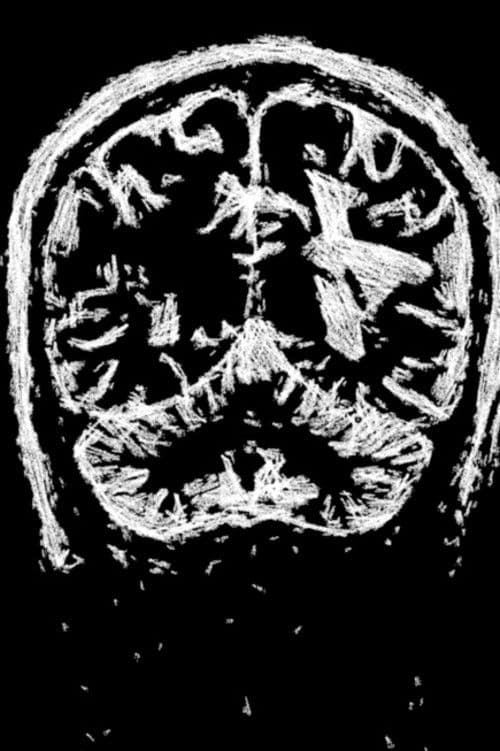

Inspired by the poem of the same name by the poet Atso Shopov, the director of the film confronts his father's terminal illness and the transience of life. The film is mainly composed of animatied MRI scans of the now late parent.